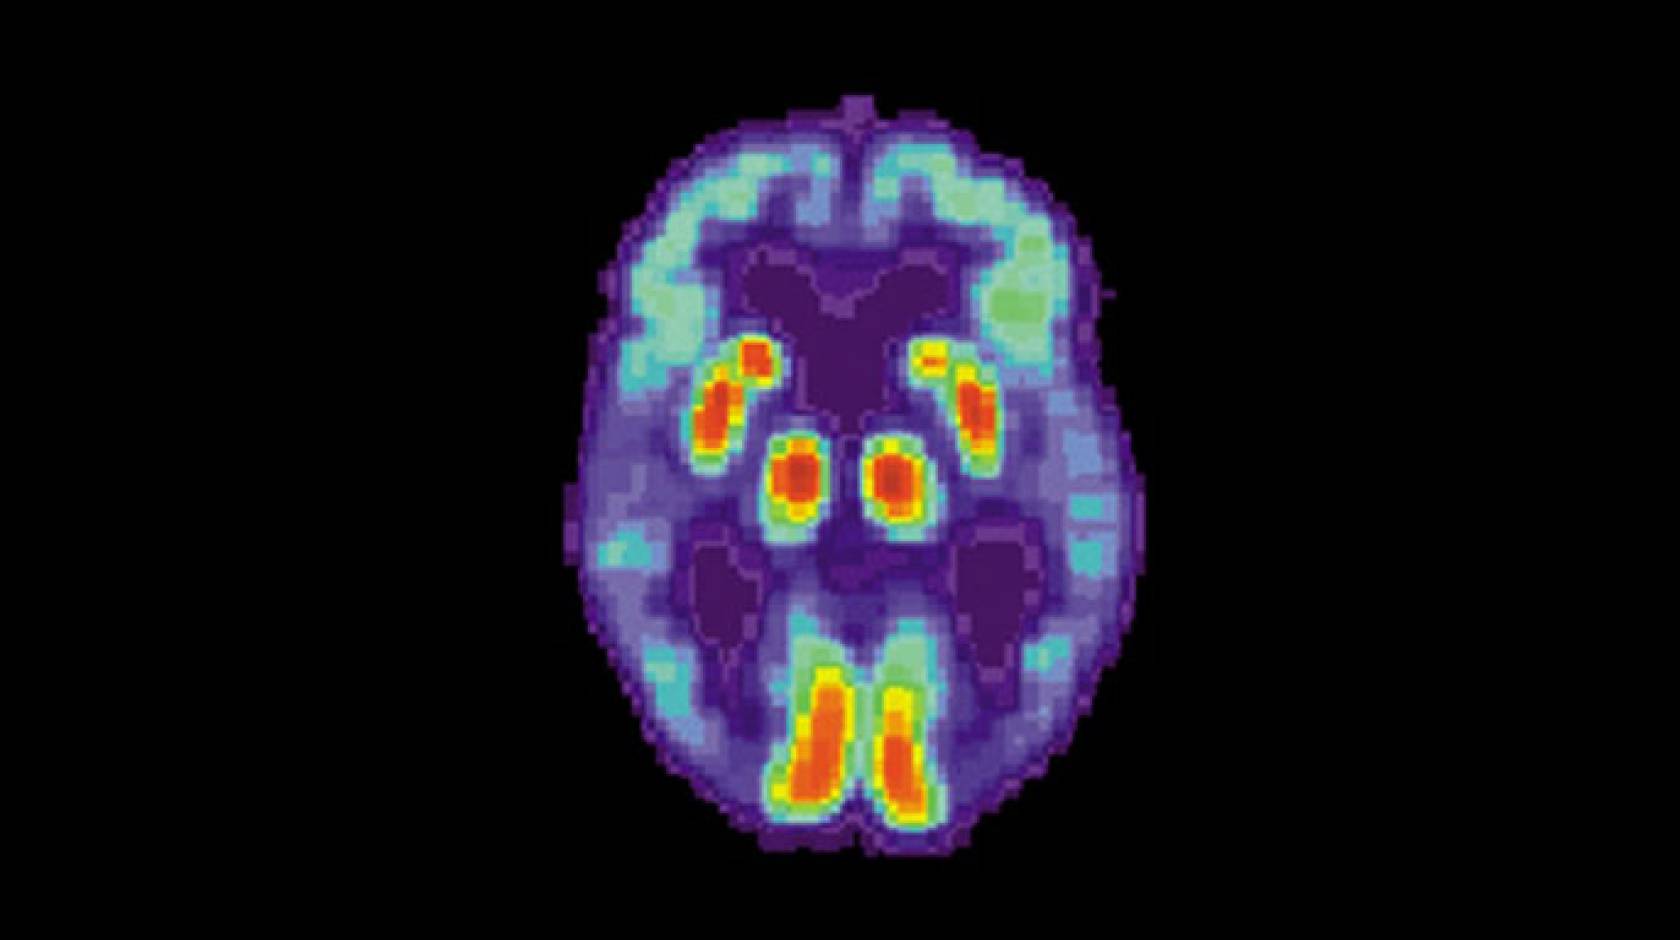

Positron emission tomography (PET) scans, which measure the levels of specific molecules, like glucose, in the brain, have been investigated as one tool to help diagnose Alzheimer’s disease before the symptoms become severe. Glucose is the primary source of fuel for brain cells, and the more active a cell is, the more glucose it uses. As brain cells become diseased and die, they use less and, eventually, no glucose.

Other types of PET scans look for proteins specifically related to Alzheimer’s disease, but glucose PET scans are much more common and cheaper, especially in smaller health care facilities and developing countries, because they’re also used for cancer staging.

Radiologists have used these scans to try to detect Alzheimer’s by looking for reduced glucose levels across the brain, especially in the frontal and parietal lobes of the brain. However, because the disease is a slow progressive disorder, the changes in glucose are very subtle and so difficult to spot with the naked eye.

To train the algorithm, Sohn fed it images from the Alzheimer’s Disease Neuroimaging Initiative (ADNI), a massive public dataset of PET scans from patients who were eventually diagnosed with either Alzheimer’s disease, mild cognitive impairment or no disorder. Eventually, the algorithm began to learn on its own which features are important for predicting the diagnosis of Alzheimer’s disease and which are not.